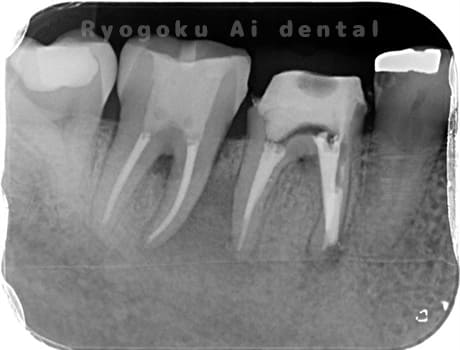

- 重度カリエス

- 抜髄治療、マイクロエンド

- 99,000円

虫歯が大きく、神経の保存ができなかったため、マイクロエンド治療を行いました。